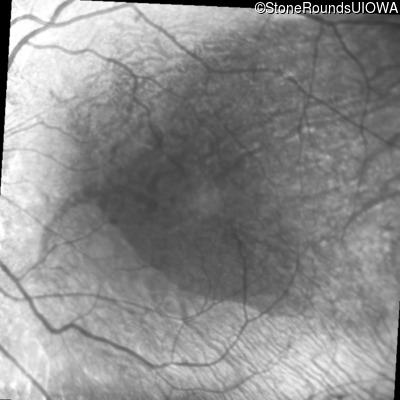

Infrared Fundus Photograph - Left - 20/63

Exemplar

Infrared Fundus Photograph - Left - 20/60